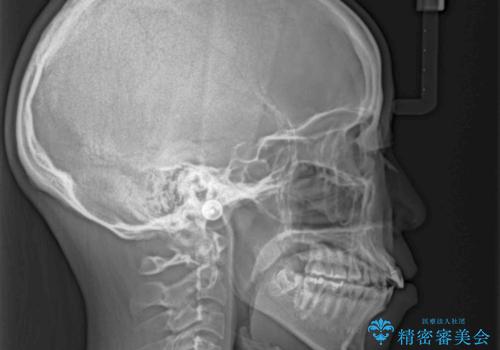

抜歯矯正の後戻り インビザラインによるオープンバイトの再矯正

- 以前矯正治療をされていましたが、後戻りが起きたことを気にして来院された患者様です。

上下前歯のオープンバイトを改善するため、インビザラインにて治療を行うこととしました。